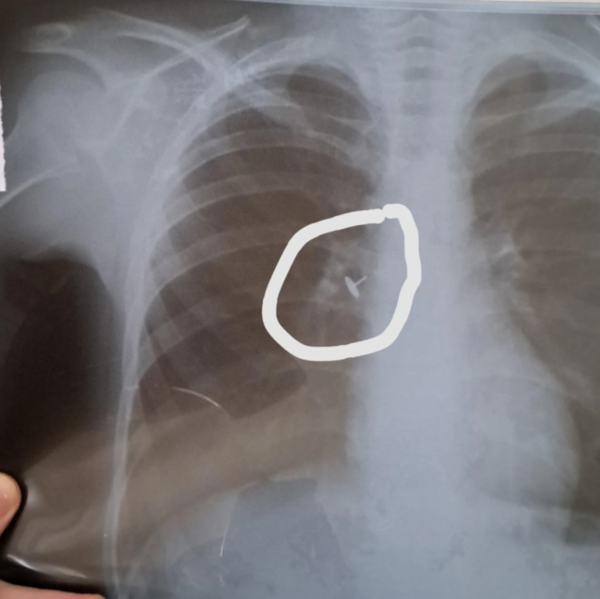

"Uşaqdan gecələr yatanda qəribə səs gəlirmiş, öskürək, xışıltı narahat edirmiş. Anası uşağı həkimə apararaq rentgen etdirib. Rentgen şəklində bronxda ilişib qalan yad cisim açıq-aşkar görünsə də, həkim uşağa soyuqlama əleyhinə müalicə yazıb. Bir aydan çox müddətdə uşağın düzəlmədiyini görən ana uşağı yenə rentgen etdirib və özü bu qeyri-adi görüntünün fərqinə varıb O, müqayisə üçün özü də ultrasəs müayinədən keçib.

Sonra mənə göndərdi ki, uşağın bronxunda olan nədir? Bu, udulmuş və nəfəs yoluna düşmüş bir knopkadır, aydın görünür. Amma necə olur ki, bunu həkim görmür, rentgen həkimi demir, uşağa soyuqlama müalicəsi yazılır? Mütləq şəkildə araşdırılmalı məsələdir. Bu məsuliyyətsizliyi edən valideyn deyil, həkimlərdir",- deyə o əlavə edib.